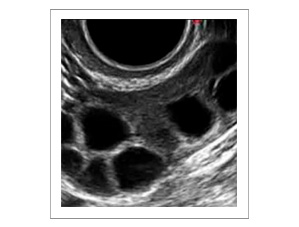

Este control del ciclo se realiza mediante ecografía transvaginal. Es importante monitorizar el ciclo mediante ecografía, sobre todo durante el primer tratamiento. La finalidad de la ecografía es evitar el desarrollo multifolicular que podría ocasionar gestaciones múltiples y/o síndrome de hiperestimulación ovárica

Imágen de folículos ováricos por ecografia